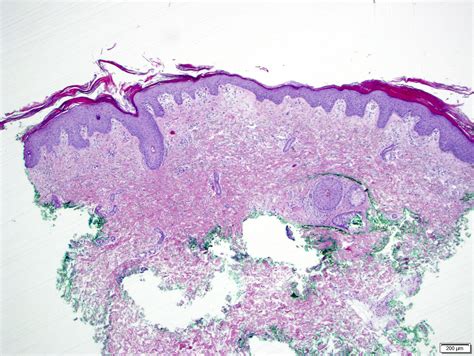

• Skin biopsy: A small sample of the affected skin is taken and examined under a microscope to confirm the diagnosis.